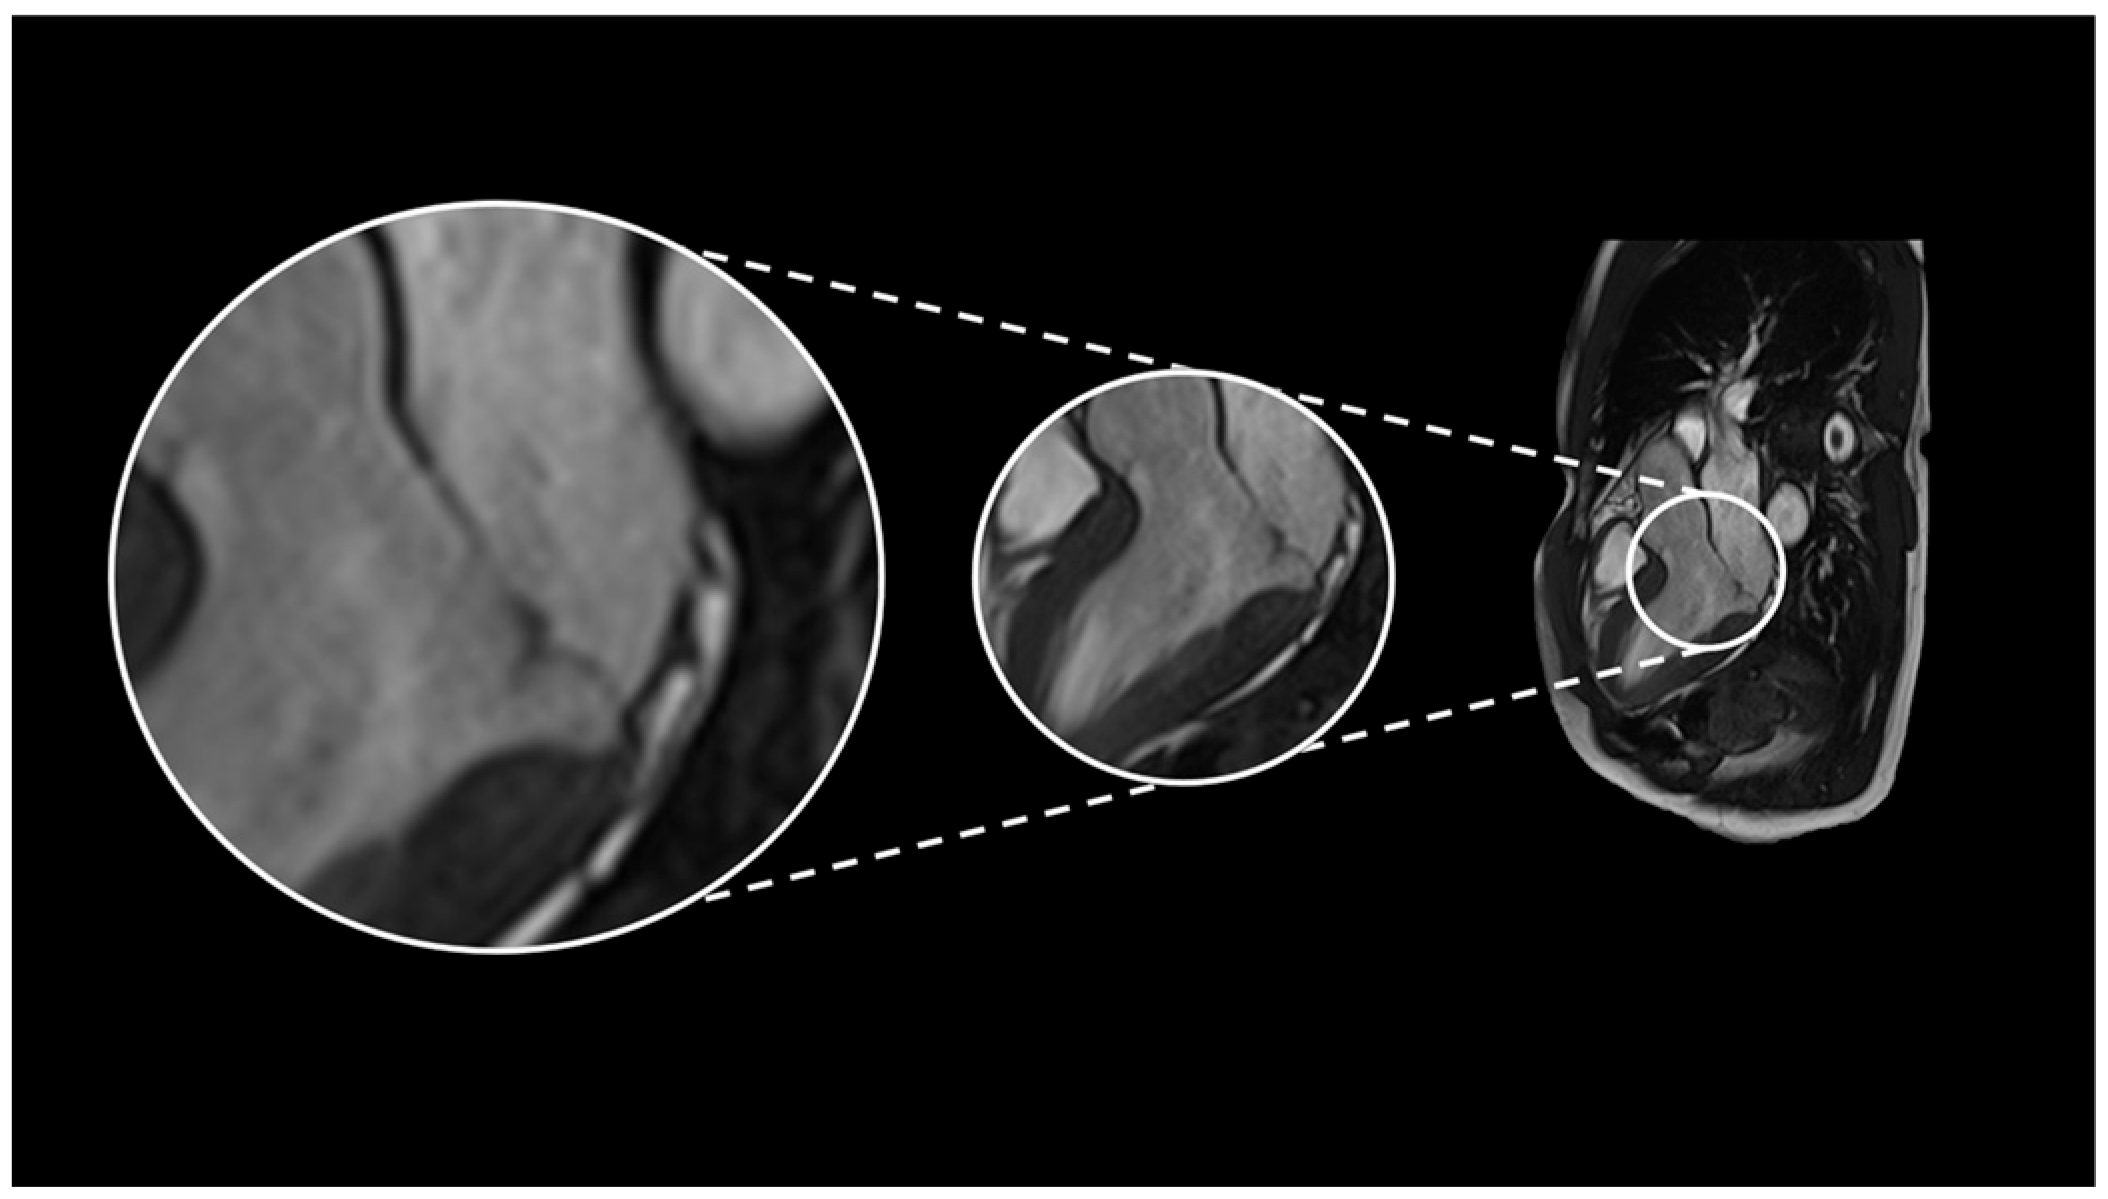

2.1. Case 1

2.2. Case 2

2.3. Case 3

2.4. Case 4

2.5. Case 5